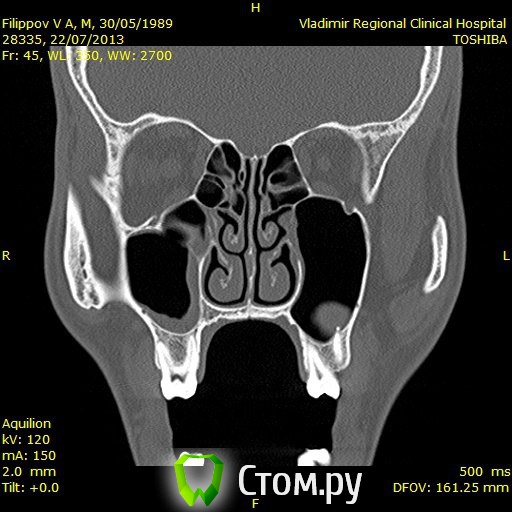

Доброго времени суток,помогите пожалуйстабеспокоит заложенность носа уже 3ий год,обший ослабленный иммунитет что выражается в частых простудах,возраст 25 лет,причина этого гдето в зубах,так как кроме этого проблем небыло никогда,когда начились эти проблему начал ходить к стомалогам мне сделали порядка 7 пломб,в одном был пульпит,как пульпит переличили стало легче но не до конца ,затем на мскт увидели кисту под депульпированной 7кой,

вот зуб пролечил у ильи мера,в 2 этапа,первый раз он сделал,и залили лекарство и сказал зуб врядли сохраним,через месяц второй прием все доделал и сказал что все хорошо,после этого общее состояние стало хуже,возможно из-за того что врач сказал что все с пульпы сливалось прямо в пазуху, вот это делали в марте ,после этого сделал мскт киста с зуба увеличилась с 1см до 1,5см, я лег в больничку местную и мнее ее вырезали,после этого прошел 1 месяц улучшений нет все также заложенность в носе и пониженный иммунитет,не подскажите что делать?кисту просто вырезали резекцую корня зуба не делали вот снимки до вырезания кисты после первого раза лечения каналов